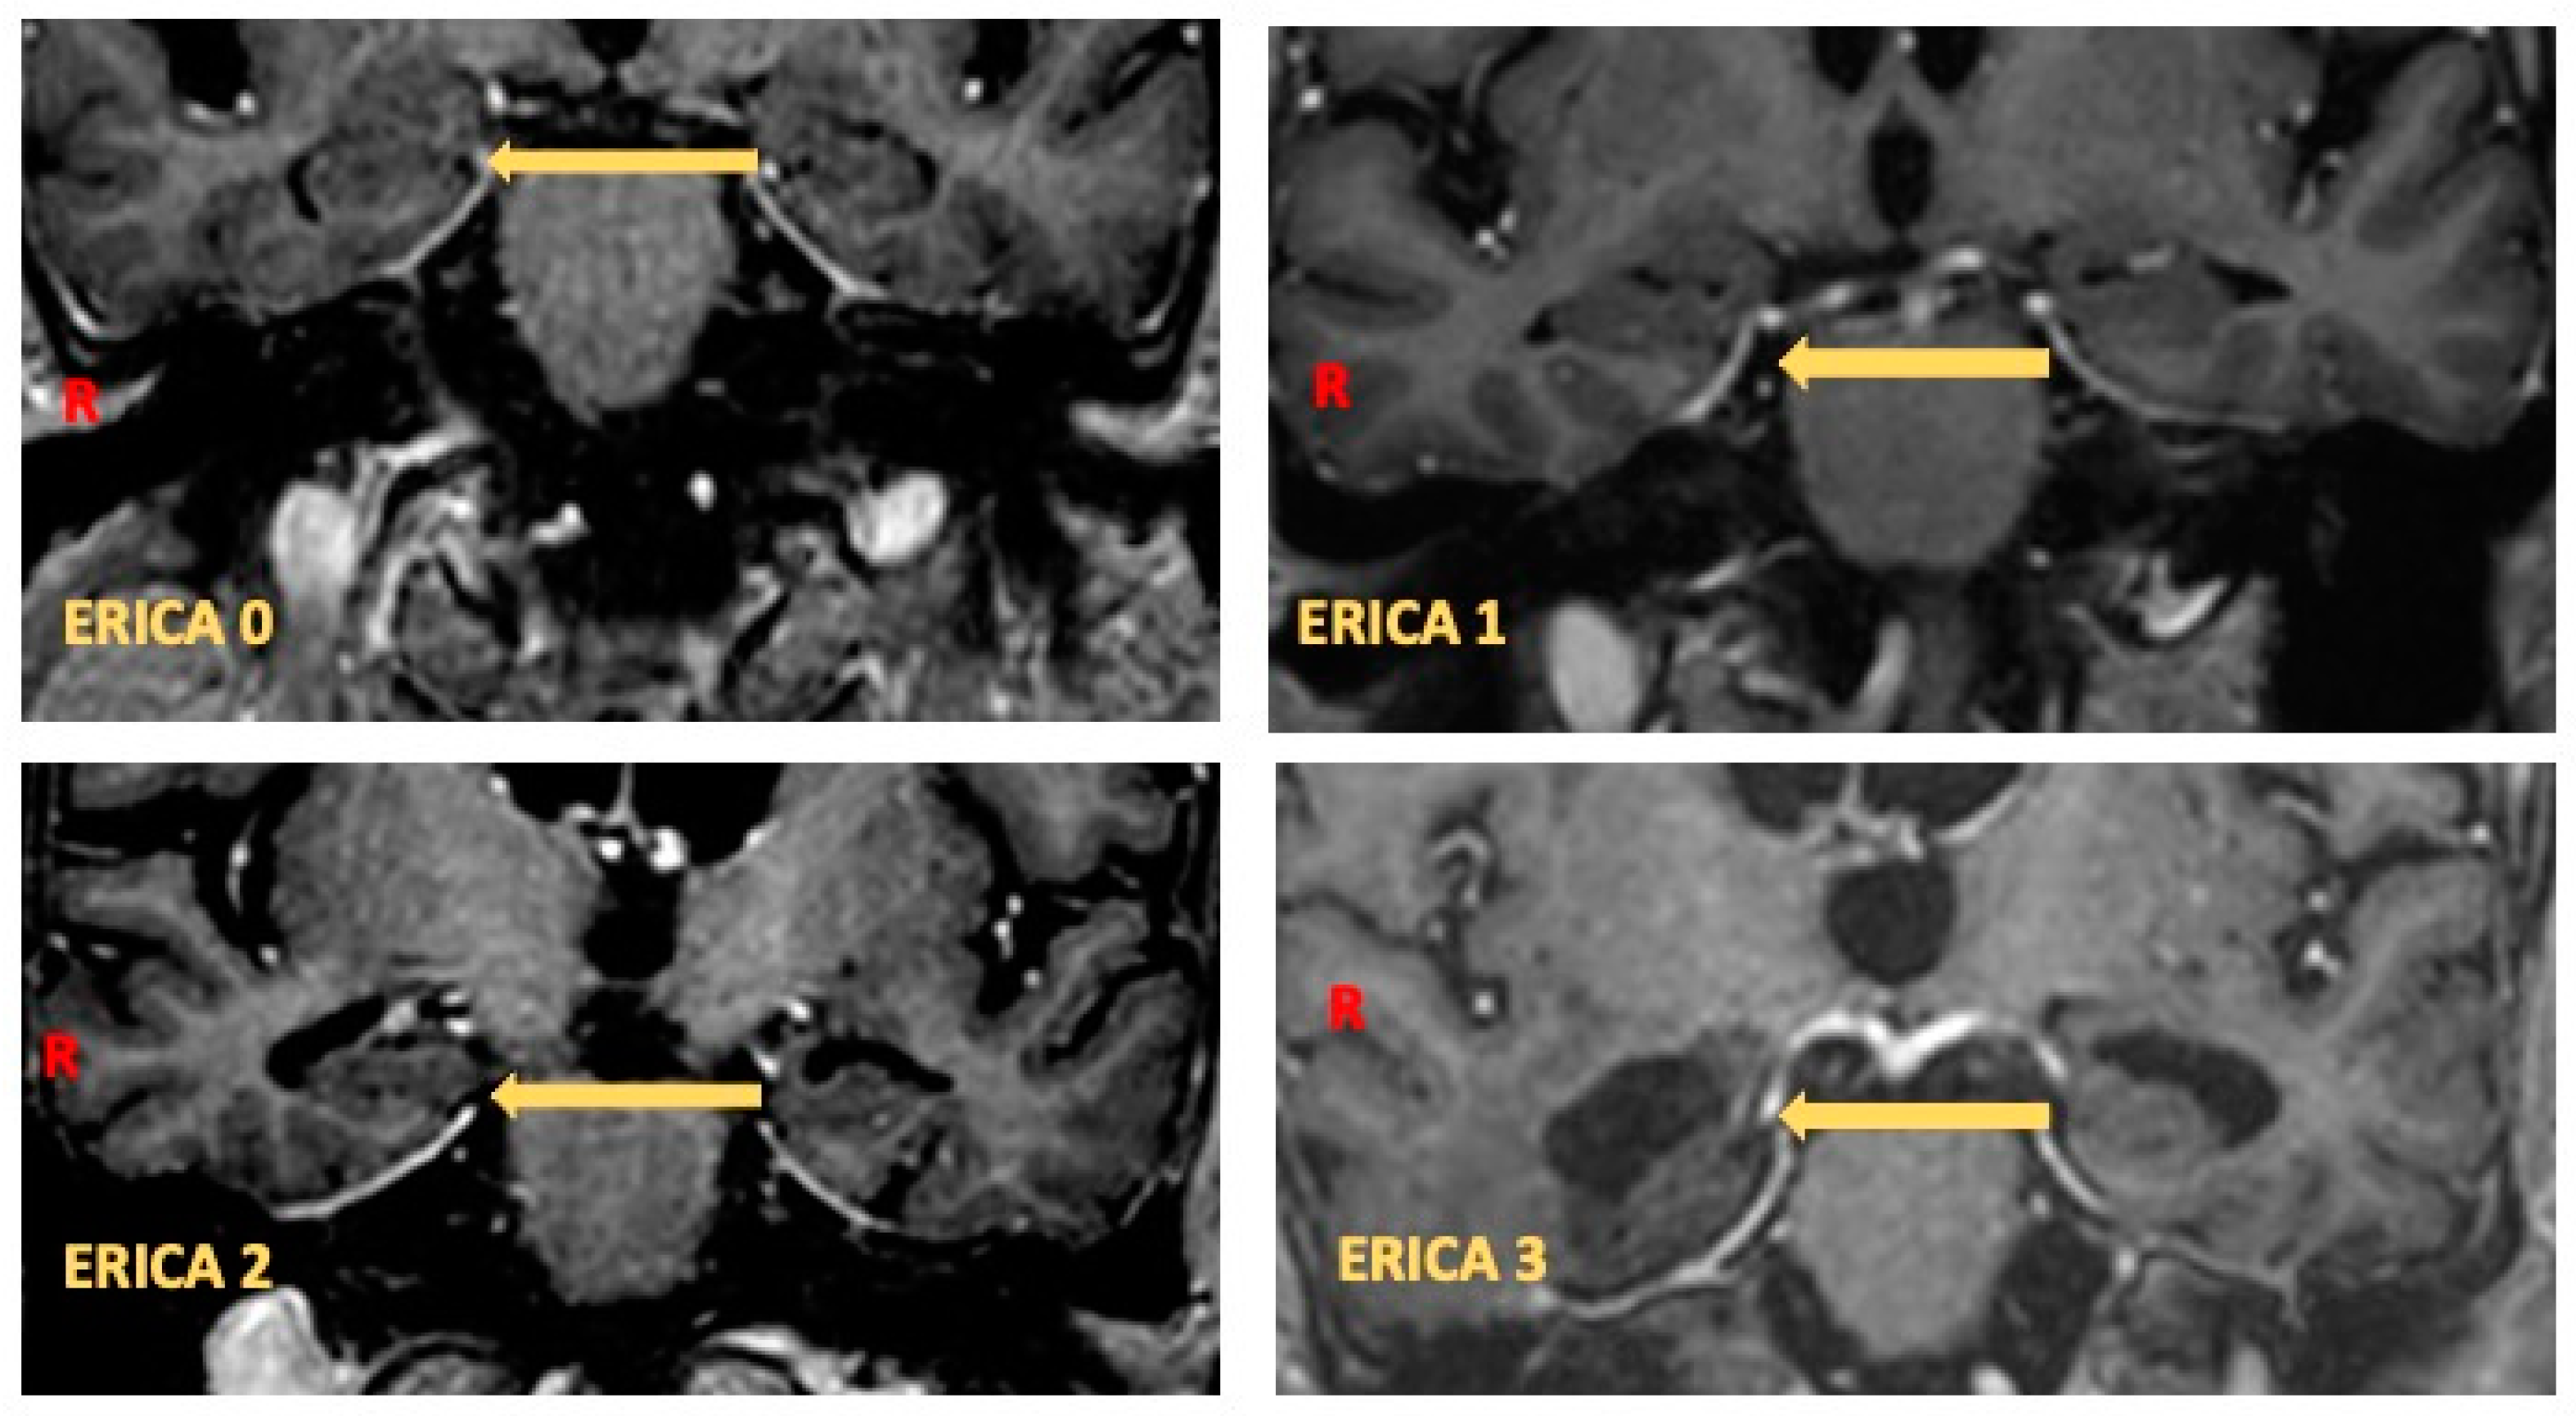

- Enkirch, S.J.; Traschütz, A.; Müller, A.; Widmann, C.N.; Gielen, G.H.; Heneka, M.T.; Jurcoane, A.; Schild, H.H.; Hattingen, E. The ERICA Score: An MR Imaging-Based Visual Scoring System for the Assessment of Entorhinal Cortex Atrophy in Alzheimer Disease. Radiology 2018, 288, 226–333. [Google Scholar] [CrossRef]

- Traschütz, A.; Enkirch, S.J.; Polomac, N.; Widmann, C.N.; Schild, H.H.; Heneka, M.T.; Hattingen, E. The Entorhinal Cortex Atrophy Score Is Diagnostic and Prognostic in Mild Cognitive Impairment. J. Alzheimer’s Dis. JAD 2020, 75, 99–108. [Google Scholar] [CrossRef]